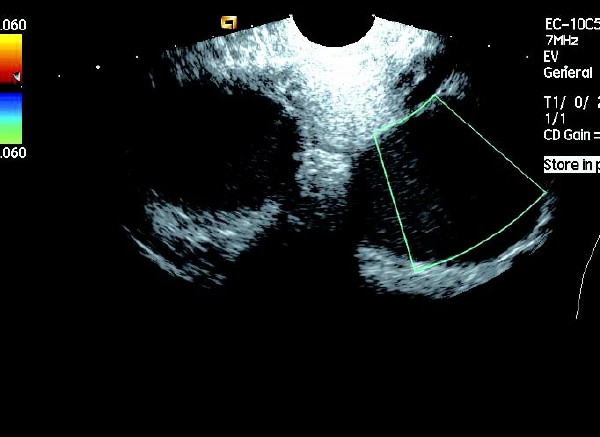

(4)CDFI 探测:囊壁及囊腔内无血流信号。

患者,女,35岁。每次月经量少,痛经,近来行经期延长、疼痛加重来院诊治。超声报告显示子宫前倾位,子宫体大小为:5.9cm×5.1cm×4.8cm,形态规则,边界清晰,宫避回声匀称,宫腔线居中,内膜厚度0.6cm,宫内未见异常回声。右侧卵巢内可见大小约5.2 cm×4.9cm的无回声区暗区,壁厚,内壁欠光滑,内见密集细光点,边界清晰。CDFI探测囊壁及囊腔内无血流信号。

超声提示:右侧卵巢巧克力囊肿